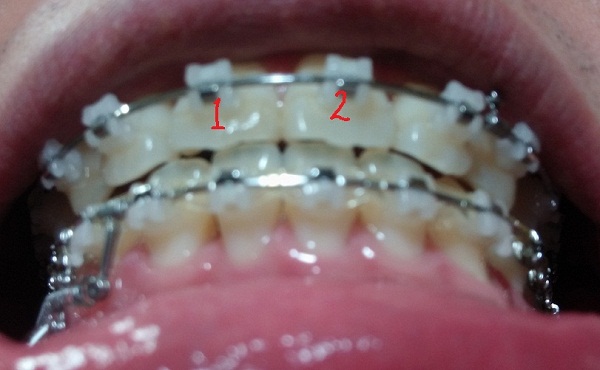

[정면]

[아래서 본 정면1]

[아래서본 정면2]

현재 교정진행상태

-중심선 99% 맞은 상태!!

-하악 파워체인으로 치아끼리 꽉 조여서 마무리로 가는 중!!

-일회용 고무줄로 치아를 다물 때, 뜨는 공간이 없게

상악 송곳니와 하악 송곳니를 당기는 중!!